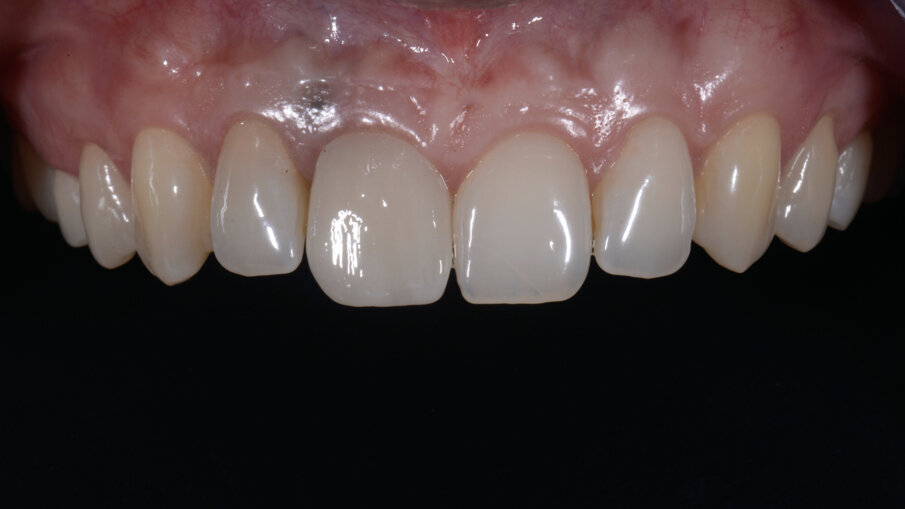

- Fresatura del dente protesico e sua finalizzazione

Il dente progettato è stato fresato utilizzando un cubetto di disilicato di litio forato e a bassa translucenza per meglio mascherare il grigiore del titanio del Tbase. Dopo avere scolpito la tessitura superficiale, il dente è stato lucidato utilizzando gomme con diverso grado di abrasività al fine di diversificare le diverse aree del dente rendendolo più naturale e in armonia con i denti vicini (Figg. 33-35). In corrispondenza della gengiva aderente è evidente un tatuaggio relativo alla posizione della pregressa fistola che potrà essere eliminato in qualsiasi momento qualora la paziente lo richiedesse. Le immagini ad 1 anno mostrano la stabilità nel tempo dell’ottimo risultato ottenuto (Figg. 36, 37).

Trascorsi quattro mesi, ad avvenuta osteointegrazione dell’impianto, il condizionamento dei tessuti appariva ottimale sia in termini di qualità dei tessuti sia in termini di volume rigenerato. I profili gengivali erano perfettamente armonici e naturali grazie al provvisorio (Fig. 29). A questo punto, dopo avere svitato il provvisorio dall’impianto, ho copiato con lo scanner intra-orale la posizione delle papille e della parabola gengivale. In tal modo, creando la cosiddetta “Maschera gengivale”, ho condiviso con il software le informazioni morfologiche necessarie per realizzare i manufatti protesici definitivi (Figg. 30, 31).